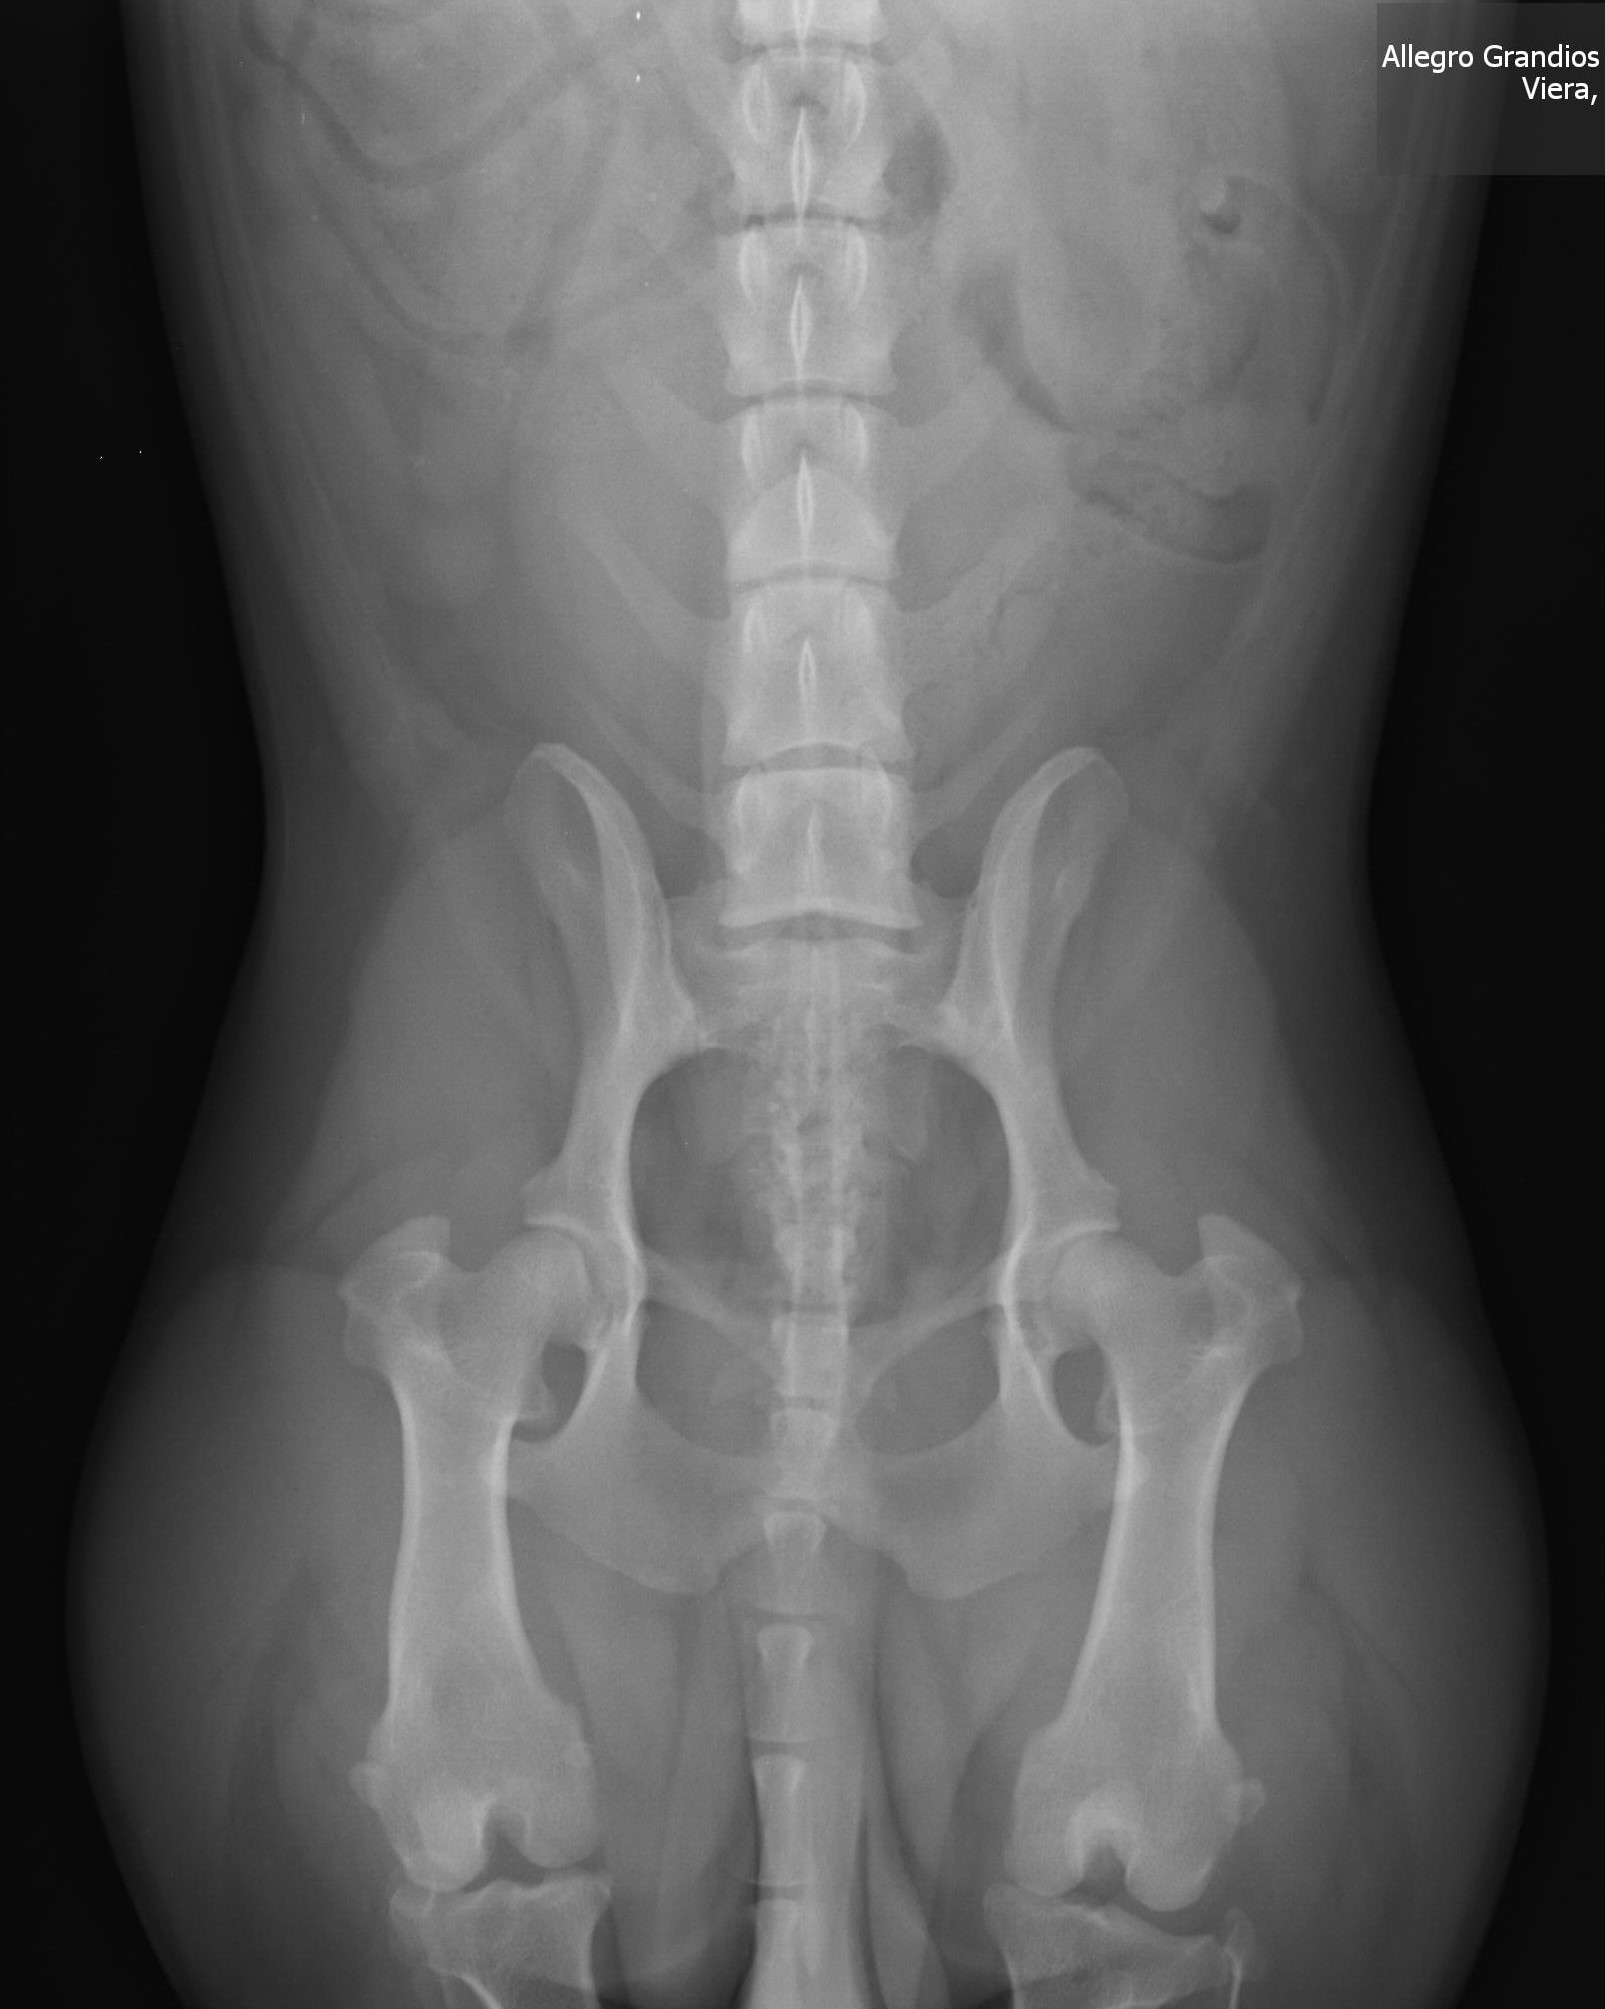

Gable Hips Perms - Copy

Gable had his hips done a few weeks ago, now that he is two we could do his permanent OFA hip xrays. OFA rated these “Fair”…